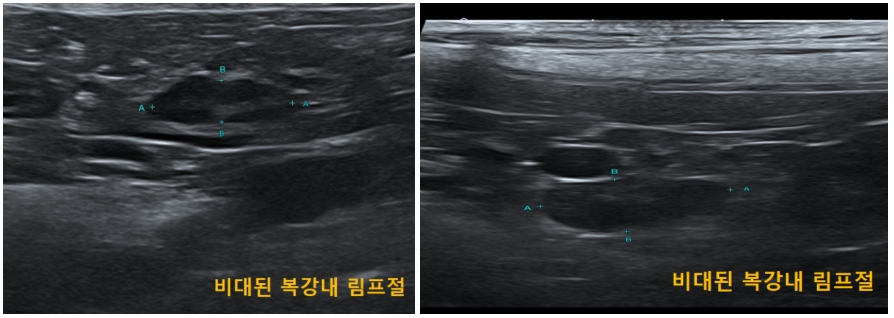

3. 영상 검사

영상검사에서는 복강내 다수의 림프절 종대가 관찰되었으며, 그 이외에 특별한 소견은 보이지 않았습니다.

3. 영상검사

진단 당시 관찰되었던 복강내 다수의 림프절 종대들 또한 항암치료 진행함에 따라 크기가 감소하였고 항암종료 이후 모두 해소되었습니다.